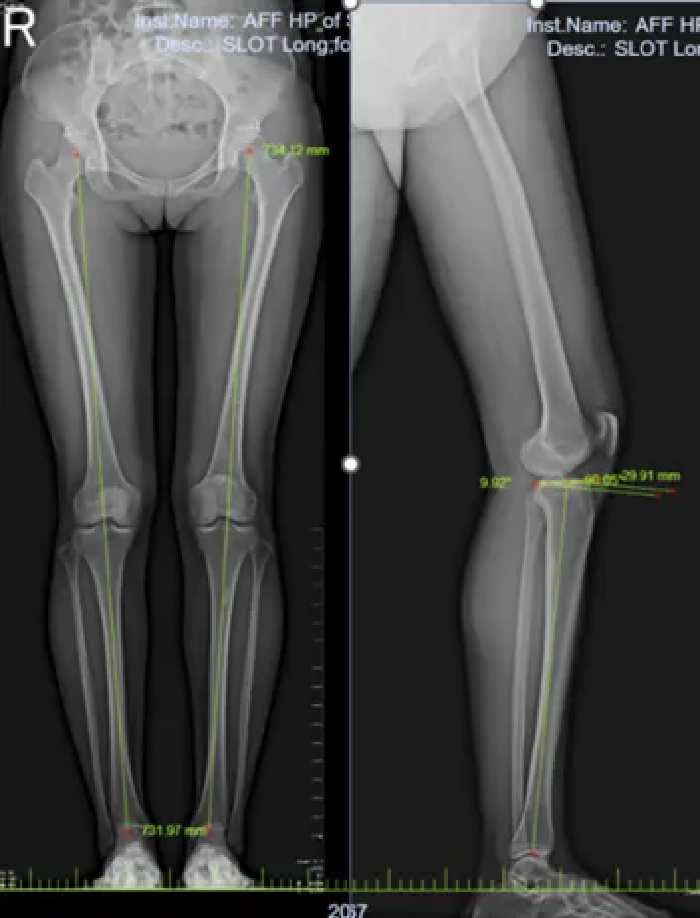

术前双下肢全长片:

左下肢力线及左胫骨平台后倾角无明显异常